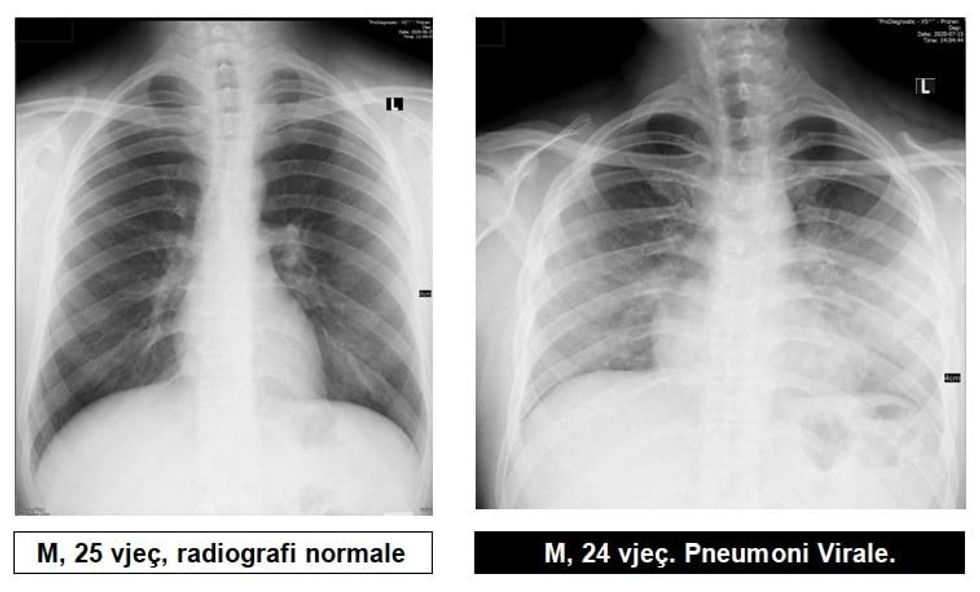

Radiologu në Spitalin Rajonal të Prizrenit, Sylejman Krasniqi tregon pamjet e mushkërive të pacientëve me pneumoni virale.

“Për te gjithë ata që maskat i kane veç si dekorim, për ata që distancën sociale e kanë diçka të huaj dhe për të gjithë ata që nuk i respektojnë këshillat e institucioneve relevante Shëndetësore, këto imazhe le të ju shërbejnë që ta kuptoni se megjithatë virus ka, pandemi ka dhe situata nuk është e mirë”, ka shkruar Krasniqi, përcjell Telegrafi.